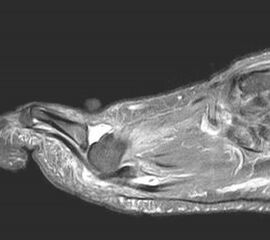

Eine Röntgenaufnahme unter Belastung mit Abbildungen des ganzen Fußes a. p. (mit 15-20° Röhrenkippung) und seitlich, sowie Schrägaufnahmen, reichen meist zur Diagnose. Manchmal ist ein MRT und DVT ergänzend hilfreich. Selten wird die Indikation für ein SPECT CT gestellt (Abb. 6).